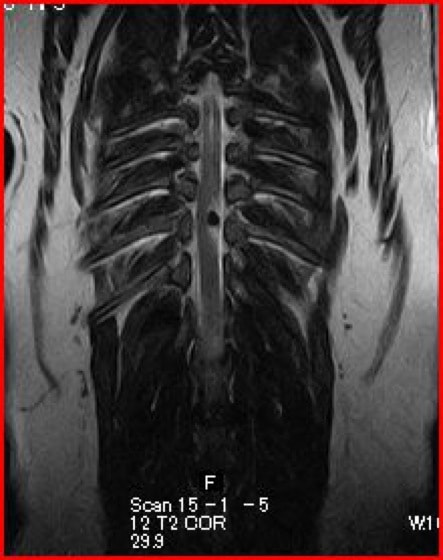

〈MRI検査:胸腰部椎間板ヘルニア〉

突然ギャンと鳴き両後肢麻痺したとのことで来院されました。触診にて腰部の圧痛を認めました。尿失禁が認められ、深部痛覚は消失していました。聴診上での異常はみられず、後肢の股圧は触知可能でした。血液検査、胸腰椎のレントゲン検査では異常を認めませんでした。MRI検査の結果、第3腰椎領域にてT1強調画像で等信号、T2強調画像で等〜やや高信号、造影剤にて均一に増強される脊髄を腹側から圧迫する腫瘤性病変を認めました。